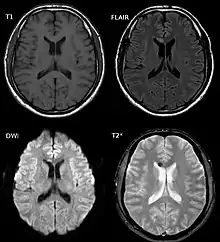

Imagerie médicale

L'imagerie par rayonnement X (Tomodensitométrie, dit scanner X) peut détecter certaines des petites hémorragies survenant simultanément à une LAD[3], mais la plupart seront invisibles et les cas de LAD non hémorragiques ne seront pas détectés. Finalement, cette technique se révèle peu sensible (de l'ordre de 25 % de cas détectés pour un échantillon riche en LAD graves)[13].

L'Imagerie par résonance magnétique (IRM) se révèle plus efficace[3],[13].

D'autres techniques pourraient s'avérer encore plus sensibles : PET, TEMP, imagerie par résonance magnétique fonctionnelle[9].